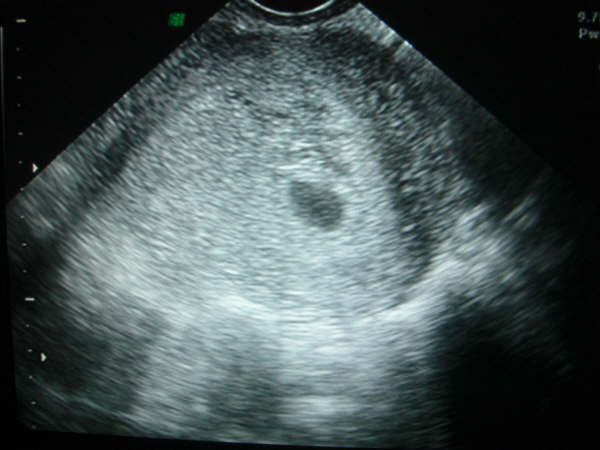

Нужно ли проходить узи на третьей неделе?

Обычно ультразвуковое обследование проводят позже, начиная с восьмой-двенадцатой недели. На ранних сроках визуализация эмбриона затруднительна из-за его маленьких размеров. Однако, если возникают боли внизу живота или кровянистые выделения, врач может назначить внеплановое узи для исключения возможных патологий.